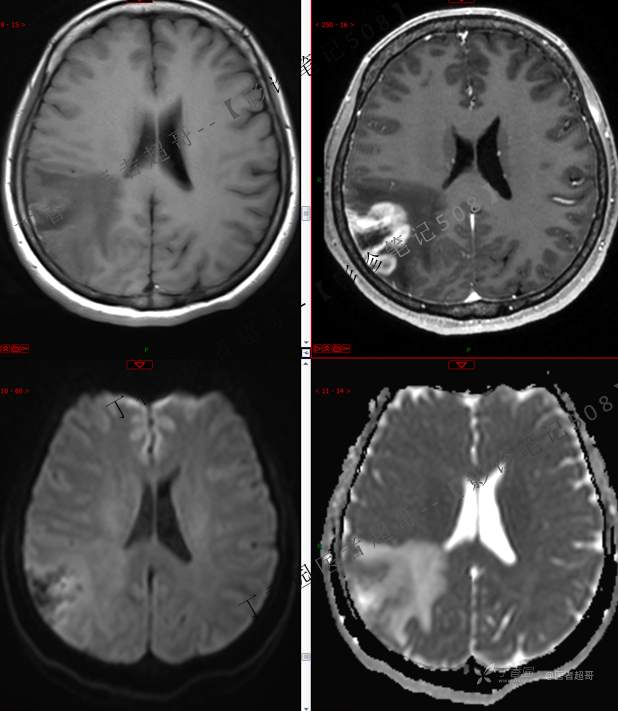

【影诊笔记508】同病异影,个人感觉有难度,欢迎分析,领丁当!有详细术程及病理!

患者性别:女

患者年龄:46岁

主 诉:突发一过性意识不清伴肢体抽搐5天余。

现病史:患者5天余前无明显原因及诱因出现一过性意识不清,伴肢体抽搐,持续约2-3分钟,后意识逐渐恢复,无明显头痛头晕,无恶心呕吐,无肢体抽搐,无呼吸困难,无二便失禁,后就诊于当地医院,行颅脑CT示“颅内占位性病变”,予以药物对症治疗,具体不详,门诊以“颅内占位性病变”,收入我科。患者自发病以来,未进饮食,近期体重无明显变化。